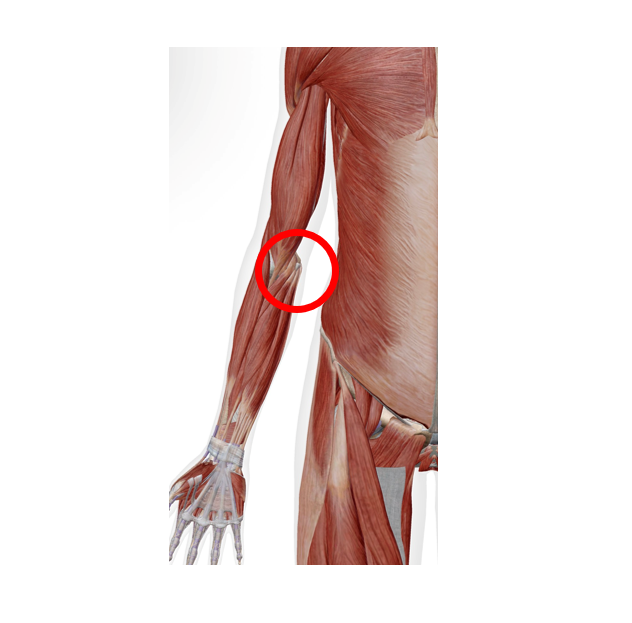

内側上顆炎

前腕の筋肉(手首を曲げる・握る筋肉) が肘の内側の骨に付いているのですが、

ここが炎症を起こしていると思われます。

痛い部位が肘の内側かつ、炎症がみられる場合は「内側上顆炎」の可能性が考えられます!

細かく診ていきましょう!ここ!肘がボコっとしているところがわかりますでしょうか。筋肉がここについているため、このボコっとしているところが痛むでしょうか?

これらの筋肉(似たような動きをしてくれる筋肉が4つほどあります!)は、

指も使って物を強く握る、前腕をひねる、手首をぐっと曲げる動作(家事・PC・筋トレなどでも)、あとは料理で包丁やフライパンなどを使ったときによく使われます。